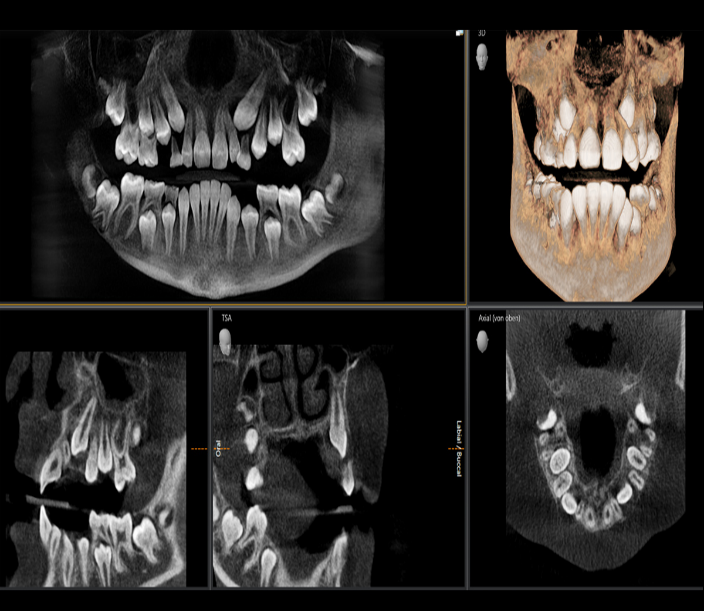

Thanks to Sharp Layer Technology (SL), high-resolution panoramic images are not only obtained in the sharp layer, but also enable analysis in the lingual/buccal plane in special cases.

This imaging device has a viewing area starting at 5cm x 5cm and extending up to 11cm x 10cm for upper respiratory tract analysis.

ORTHOPHOS SL 2D, with DCS (Direct Conversion Sensor) sensor and SL technology, provides images that satisfy even dentists with high demands for panoramic imaging. With its 3-point head immobilization, balanced arms, and patented occlusal bite rod, it guarantees unique resolution in every image. Together with the pioneering SIDEXIS 4 software, it offers a unique variety of innovative solutions for clinical workflow.

- Thanks to the Sharp Layer Technology (SL) technology, high-resolution panoramic images are not only obtained in the sharp layer, but also enable interactive analysis in the lingual/buccal plane in special cases.

- Daha kesin tanılar, net açıklamalar: 3D görüntülemenin bir çok avantajı vardır.Üstüste binmiş dişler,umulmadık sinir kanal geçişleri,gizli kökler,gömülü diş veya temporomandibular eklem vakalarında 3D görüntüleme özelliği ile çok sayıda paha biçilmez değerde tanı olanağı sağlamaktayız.